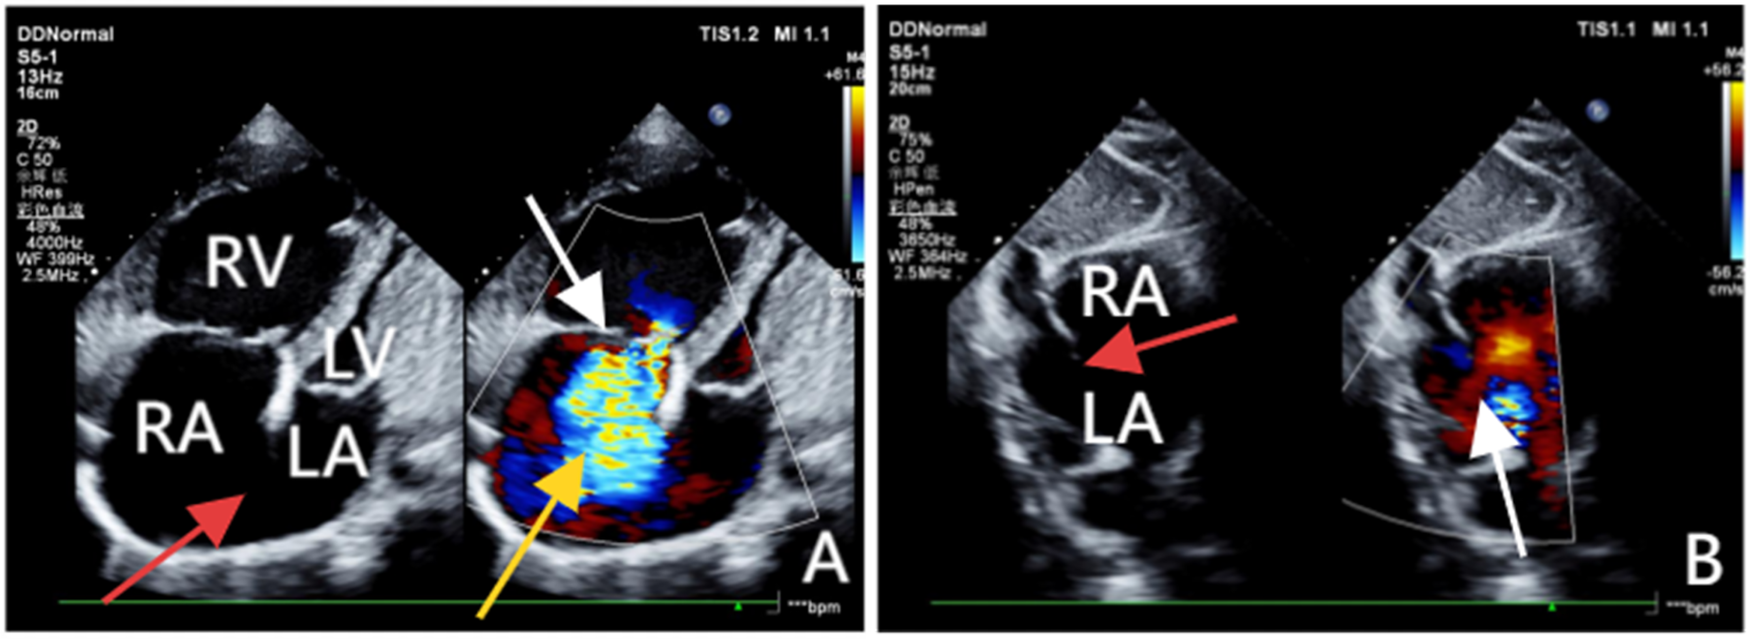

Transthoracic echocardiography (TTE) revealed an atrial septal defect (ASD) with a 3 cm opening (Figure 1), along with partial anomalous pulmonary venous drainage. Pulmonary artery systolic pressure (PASP) was 147 mmHg by measuring the tricuspid regurgitation spectrum using continuous Doppler., and severe tricuspid regurgitation, the inner diameter of the main pulmonary artery widened slightly, about 3 cm, left ventricular ejection fraction(LVEF) 69% were noted. Coronary CT angiography (CTA) confirmed these abnormalities and revealed a multi-fenestrated ASD (measuring 2.8 × 3.1 cm and 1.8 × 1.9 cm), the dorsal and basal segmental branches of the right inferior pulmonary vein drain abnormally into the inferior vena cava at its junction with the left atrium. Chest and abdominal CT angiography (CTA) further confirmed the IVC anomaly draining into the left atrium (Figures 2, 3). Right heart catheterization confirmed severe pulmonary hypertension, revealing a pulmonary artery pressure of 117/40 mmHg (mean 60 mmHg). While a full set of hemodynamic measurements including cardiac output was not obtained during the procedure, the documented pulmonary artery pressures were sufficient to establish the diagnosis of severe PAH and guide the initial therapeutic strategy (Figure 4).

Figure 1

(A) Obtained via left lateral decubitus transthoracic echocardiography, comprises two images. The left panel, a two-dimensional view, clearly demonstrates a loss of continuity in the atrial septum and enlargement of the right atrium and ventricle. The right panel, a Doppler ultrasound, highlights the tricuspid valve (white arrow) with a jet of regurgitant blood flow across it (yellow arrow). (B) Acquired from the subcostal window with the patient in a supine position, clearly reveals the discontinuity in the atrial septum (red arrow) and a left-to-right shunt across the defect (white arrow).